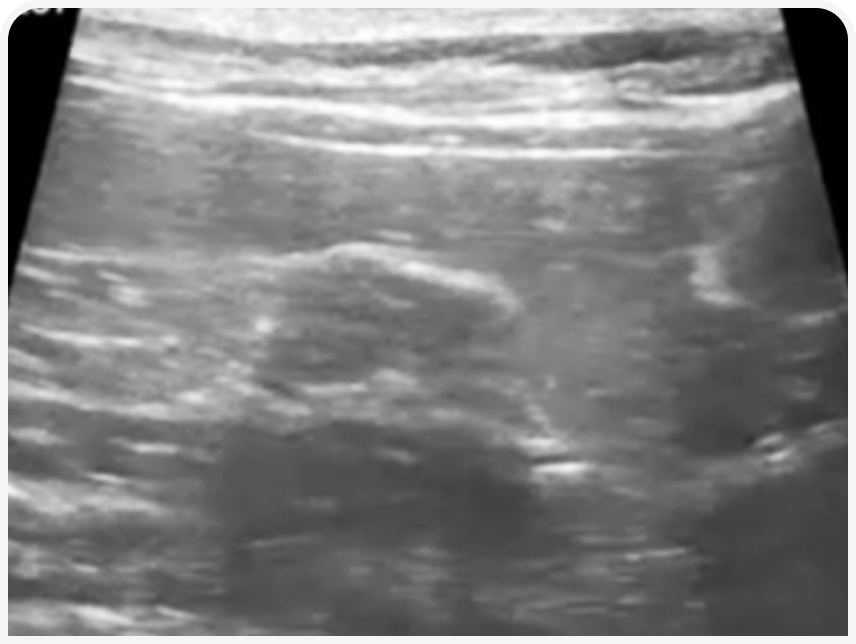

Культя матки и краниальной части влагалища у собак и кошек в течку под действием эстрогенов значительно утолщается за счет отека, стенки становятся гипоэхогенными, картина отличается от периода полового покоя.

Также при ОРС можно обнаружить пиометру культи матки (развивается у сук с ОРС под действием половых гормонов, в отличие от культитов, которые в первую очередь являются следствием реакции на неподходящий/инфицированный шовный материал).

Но, как и у сук, в течку яичники будут иметь характерную картину овального образования с множеством кистозных структур размером до 3-4 мм, а культя матки будет утолщаться. Алгоритм проведения исследования аналогичен алгоритму у сук.